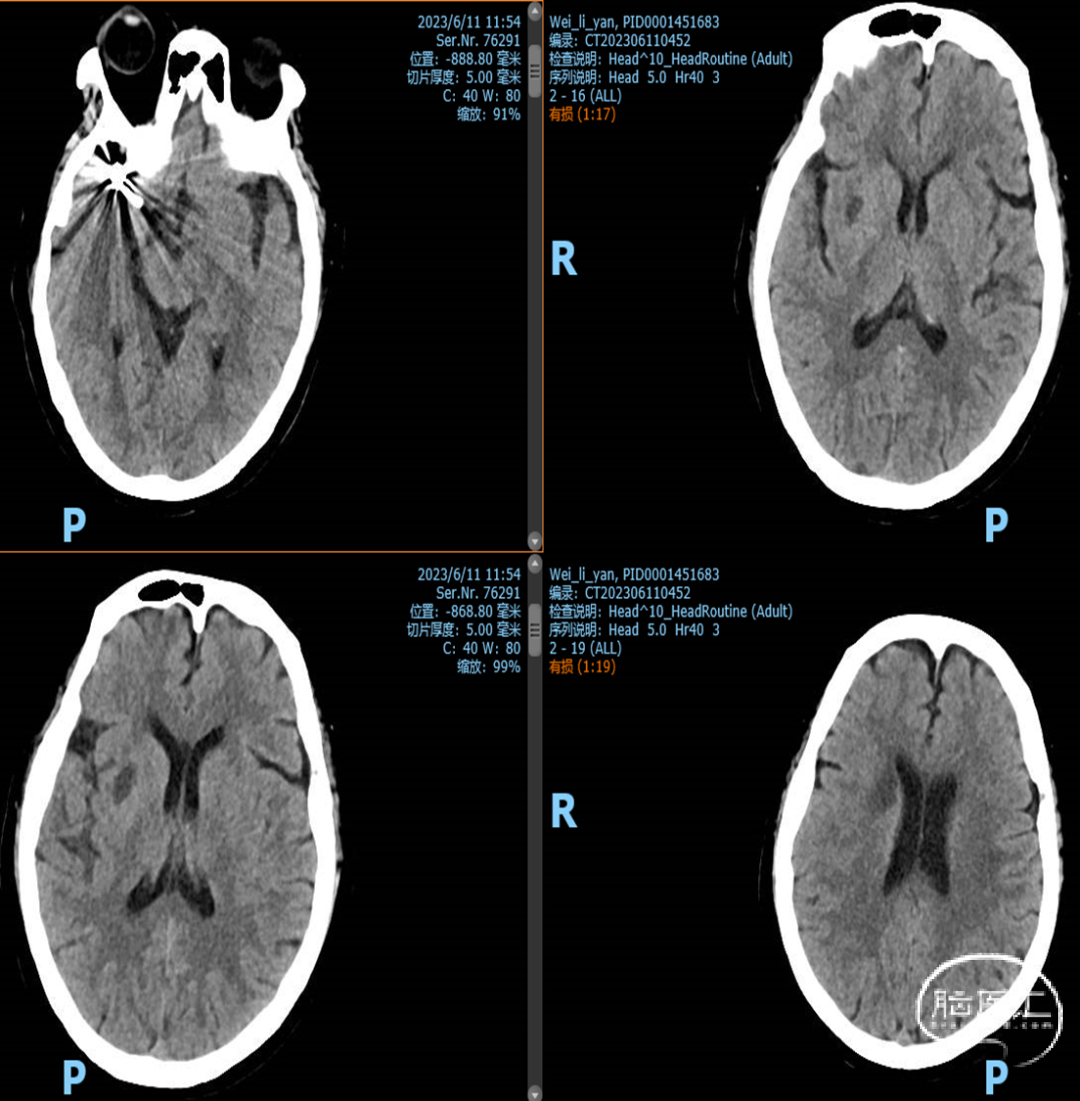

一般项目:患者女 年龄:71岁;

因“检查发现脑内动脉瘤10天”入院;

外院造影检查发现右侧大脑中动脉M1段动脉瘤、右侧颈内动脉眼动脉段动脉瘤。

既往史:既往有高血压、糖尿病病史。